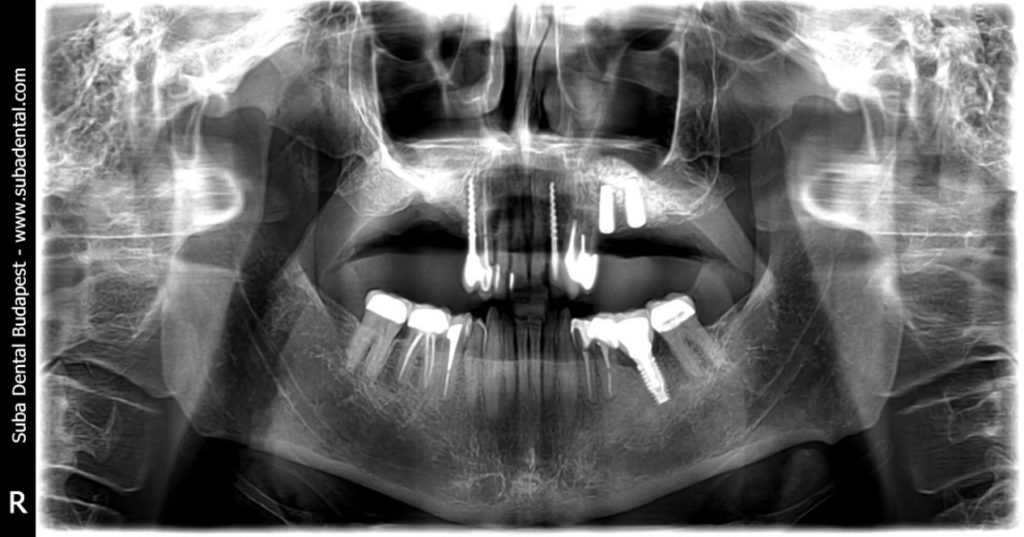

Kontroll panoráma-felvétel az elvégzett kezelésekről, a bal oldali felső 2 implantátumról és a csontpótlásról (sinus lift). Jobb oldalon (önnek a balon) látszik, hogy a régi implantátumot már eltávolítottuk (explantáció)

- A jobb oldalon a 17-es (legutolsó) implantátumot eltávolítottuk (explantáció), és a helyét, valamint a mellette lévő rosszul gyógyult foghúzás helyét sebészileg kitisztítottuk. Ide ekkor még nem kaphatott implantátumokat a gyulladás miatt. Csak a 4-6 hónap gyógyulási idő elteltével lehet visszatérni ennek a régiónak a további kezelésére.

- A bal oldalon, az alacsony csontmagasság miatt csontpótlást kellett végezni (sinus lift), majd ugyanebben az ülésben be is helyeztünk 2 db implantátumot. Csontpótlásos fogbeültetés esetén minimum 6 hónapot várunk a végleges koronák/hidak elkészítésével!